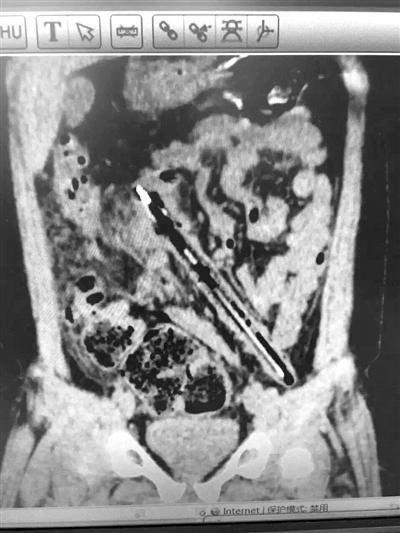

磁共振结果显示,肠子里15厘米的笔赫然可见

昨天中午12:45,浙大儿院普外科副主任医师高志刚在朋友圈里发了一张磁共振片子的照片——一根筷子模样的东西,直直地卡在肠子里。高医生还写了一句:“整支笔在肠子里,已经一个月了!”马上联系高医生,得知这是他上午接到的一个病例,一个小男孩把一支15厘米的笔从肛门里塞了进去,而且已经在他肠子里待了一个月!

昨天一大早,男孩父母带着孩子从台州赶到浙大儿院,磁共振结果显示,一支15厘米的笔,确实卡在男孩的结肠里,且两端笔头抵着肠子的地方,已经有了炎症!